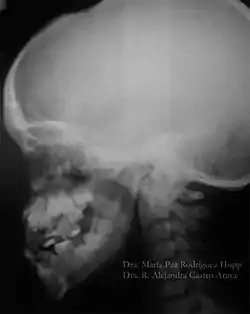

O diagnóstico do portador de DCC é realizado através de exames clínicos e radiográficos. A aparência clínica dos acometidos é bastante característica, principalmente após a puberdade devido a alguns traços dessa doença, como baixa estatura, falha na erupção dos dentes permanentes, dentes supranumerários e retardo na esfoliação dos dentes decíduos. Outros aspectos dessa patologia são: a aplasia ou hipoplasia clavicular (clavículas rudimentares ou completamente ausentes), que está presente em 10% dos casos, que permite o movimento do braço até ao plano sagital mediano. A abóboda craniana aumentada, uma menor espessura do músculo masseter, hipodesenvolvimento do terço médio da face, geralmente também é apresentado uma hipoplasia da maxila, retardo no desenvolvimento esquelético, o pescoço largo e atraso no fechamento das suturas cranianas. Em alguns casos é possível observar que os palatos estreitos e profundos também são frequentes. É importante realizar o diagnóstico diferencial devido aos pacientes exibirem nanismo, ossos densos, frágeis e agenesias parciais das falanges dos dedos dos pés e mãos.[9][10]

O atraso na erupção dos dentes pode ser explicado pelo aumento na densidade óssea de algumas regiões dos maxilares, em decorrência de uma remodelação anormal do osso; ausência ou diminuição do cemento celular; aumento da espessura da fibromucosa; presença de dentes supranumerários; formação incompleta da lâmina dentária e ausência de rizólise dos dentes decíduos. Jensen e Kreiborg (1993a, 1993b) têm relatado anormalidades morfológicas na maxila e mandíbula destes pacientes. Na maxila, os seios paranasais podem estar pequenos ou ausentes. Na mandíbula, os ramos ascendentes apresentam-se paralelos entre si e os processos coronóides mostram uma curvatura para a distal, além da persistência da sínfise mandibular. Também na face, os ossos nasais são hipoplásicos ou ausentes e os zigomáticos, hipoplásicos.

Sabe-se que a retenção prolongada dos dentes decíduos, agenesias e dentes supranumerários provocam má oclusão. Portanto, procedimentos ortodônticos devem ser utilizados com a finalidade de adequar a cavidade bucal para futura reabilitação protética. Os exames radiográficos, além de auxiliar na detecção das anormalidades maxilofaciais, permitem o acompanhamento dos pacientes, sendo, por isso, considerados uma ferramenta para o diagnóstico e conduta terapêutica.[11]